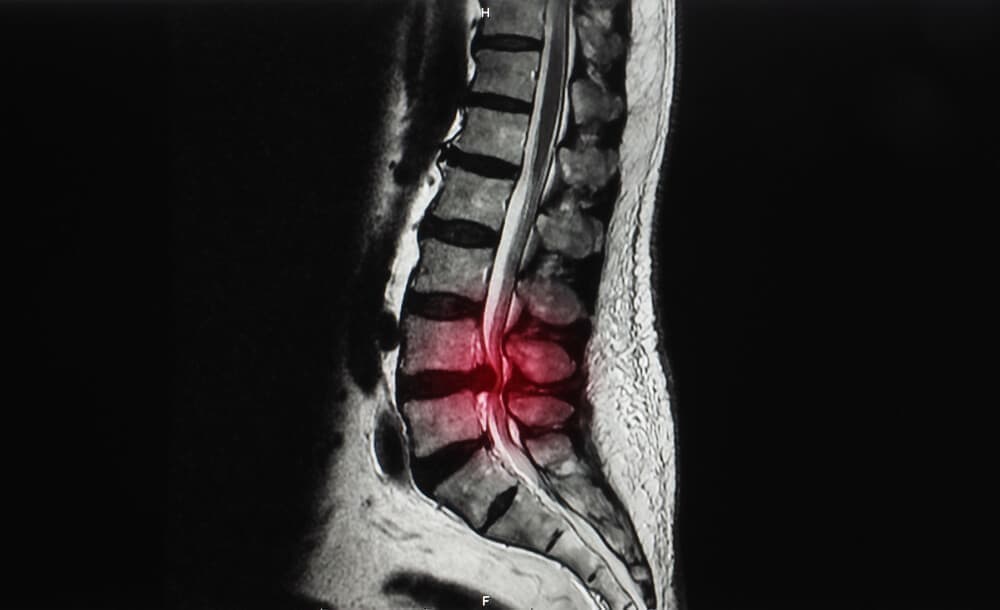

Before

脊柱管狭窄症とは?

体を支える脊柱は、椎骨という骨が連結してできています。

その椎骨には穴が存在し、脊柱として形成されたときには脊柱管という脊髄・血管が走る道が作られます。

その脊柱管が加齢や何かの要因でズレが生じ狭まったときに発症するのが脊柱管狭窄症です。

脊柱管が狭くなると、内部を走っている脊髄や血管が押し付けられます。

それにより

痛みやしびれといった症状が現れます。